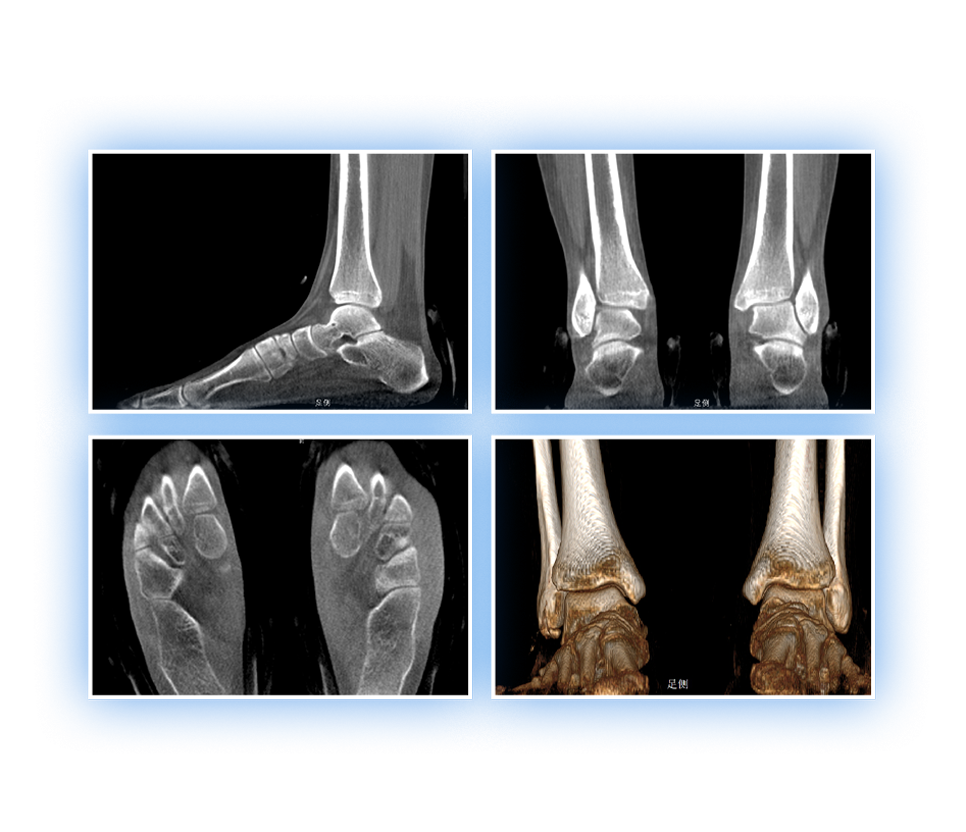

· 补位CT,提供负重位三维影像

· 引领普放走向三维精准诊断时代

足踝

精准诊断

手术方案规划

术后随访

VR体绘制重建